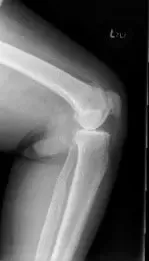

His physical examination revealed tender joint movements with crepitus. There was tenderness on the medial joint line and medial patellar facet. Imaging studies revealed bicompartmental Osteoarthritis of the knee with joint space obliteration of the medial compartment and the patellofemoral compartment.

Pre operative X-Ray of the left knee showing AP and lateral views